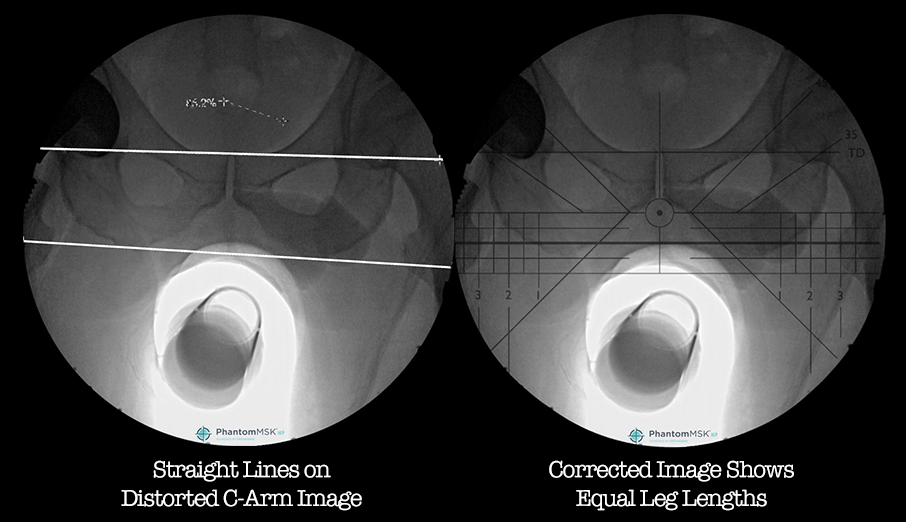

distortion-correctionPress Releases

OrthoGrid Systems’ PhantomMSK™ Platform Receives FDA 510(k) Clearance for Novel Distortion Adaptation Technology in Orthopedic Surgery

February 26, 2019 New regulatory clearance in USA further expands the clinical utility of OrthoGrid’s…